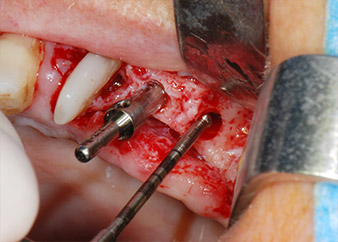

Prima di procedere al posizionamento dell'impianto, il tessuto infetto è stato rimosso dall'osso alveolare nel sito di impianto e attorno ai denti di appoggio con un attacco progettato per la sagomatura ossea e per la raccolta di frammenti ossei (Piezomed, attacco B5) (Figg. 6 e 7).

Le sedi di impianto sono state preparate in corrispondenza dei siti 25 e 26 con strumentazione rotante, utilizzando un manipolo contrangolo con una velocità di trasmissione 20:1 con motore potente di nuova generazione (Implantmed di W&H) (Fig. 8).